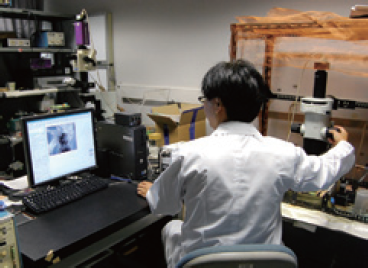

▲心臓のリアルタイムカルシウムイメージングの様子